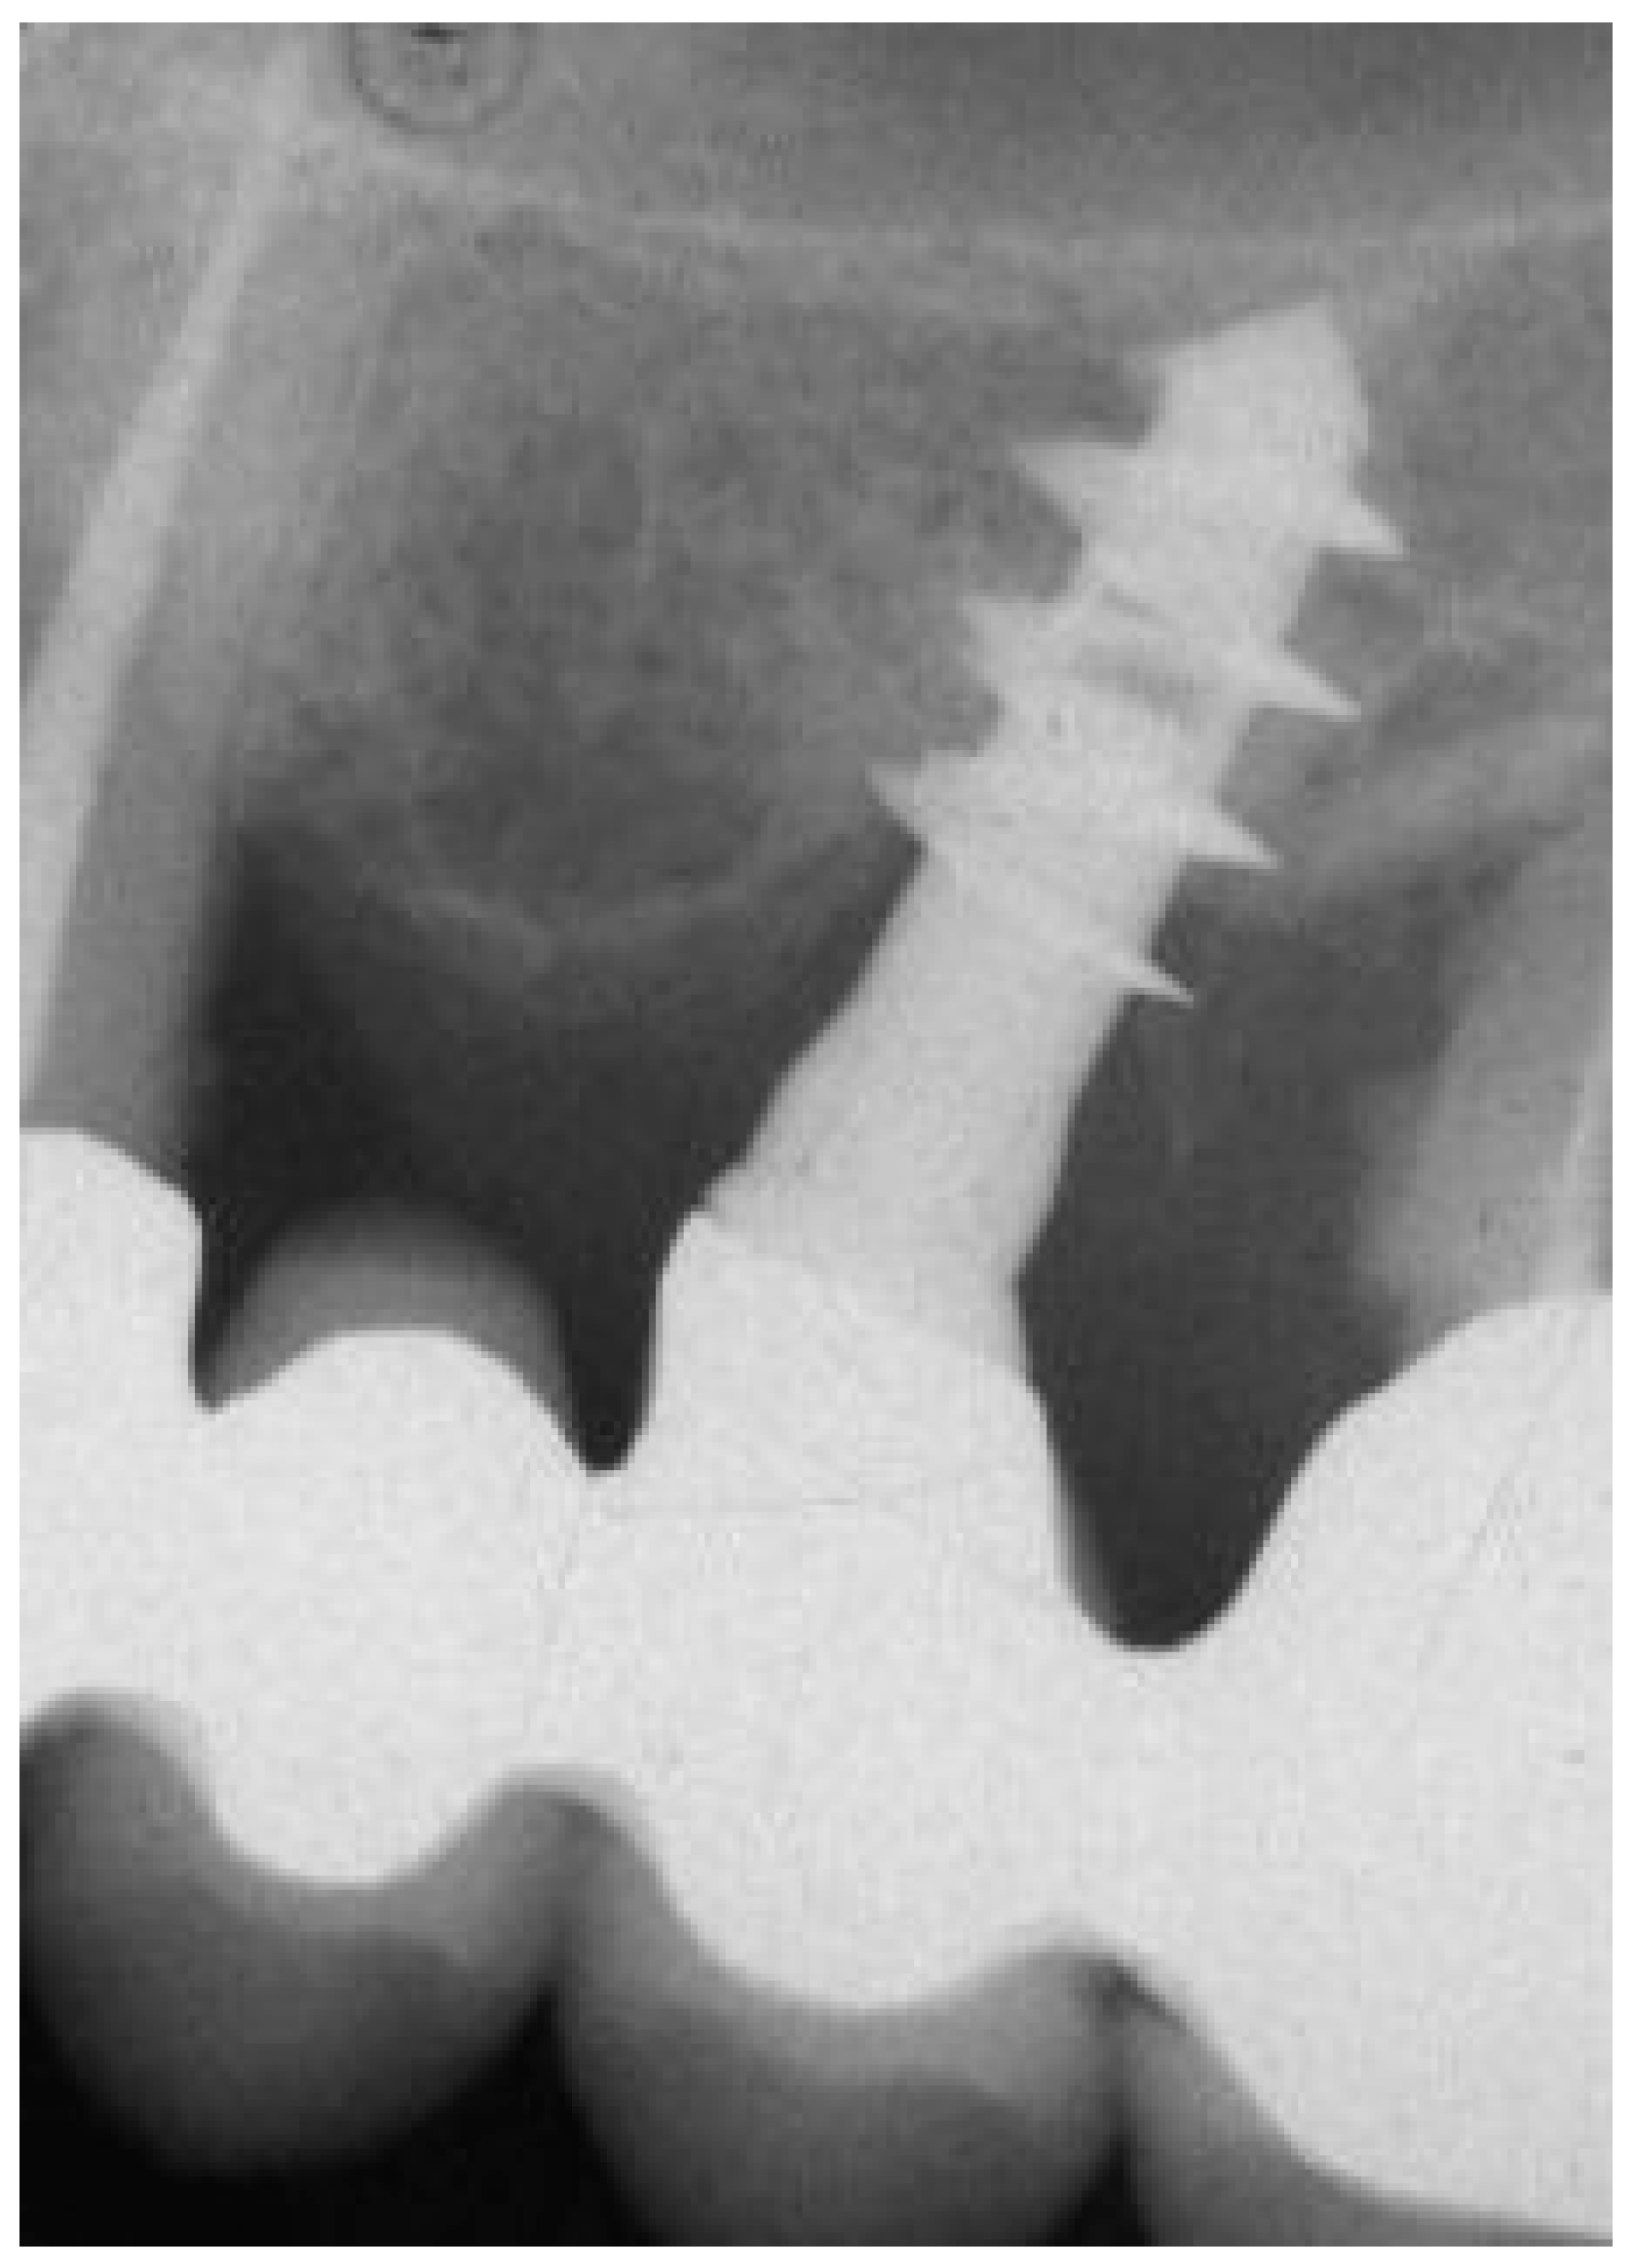

2.1. Implant Retrieval and Case Overview